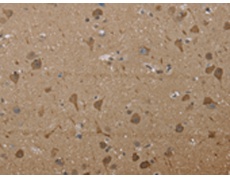

IHC positive control: |

Human brain and human ovarian cancer |